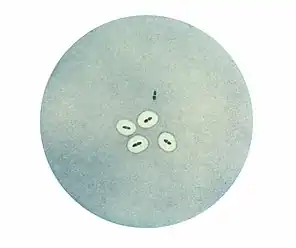

Morphologie

Observé au microscope, le pneumocoque se présente sous forme de diplocoques à Gram positifs lancéolés accolés par leur côté pointu, formant un chiffre 8. Dans les produits pathologiques, les pneumocoques pathogènes sont entourés d'une capsule bien visible[2].